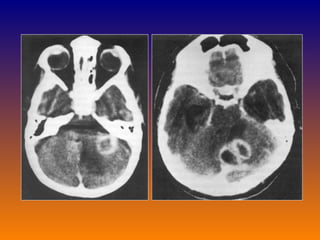

Subarachnoid hemorrhage CT scan: Small bleed may be missed in CT (10%) After 7 days CT may be normal in 50% cases CSF examined if CT normal it should not precede CT Lumber puncture: opening pressure high Definitive: RBC >100,000/cmm Xanthochromia-develops in 1-2 days MRI sensitive for bleed >10 days old useless for acute investigation

Subarachnoid hemorrhage CTscan: Small bleed may be missed in CT (10%) After 7 days CT may be normal in 50% cases CSF examined if CT normal it should not precede CT Lumber puncture: opening pressure high Definitive: RBC >100,000/cmm Xanthochromia-develops in 1-2 days MRI sensitive for bleed >10 days old useless for acute investigation